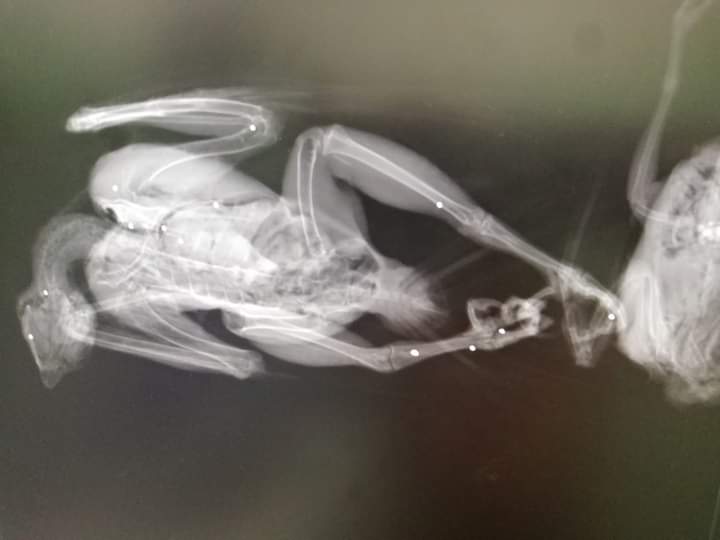

«Una mattanza: Falco pellegrino ritrovato a Leverano, impallinato e ucciso subito dopo aver predato» è riportato in un post di SOS Fauna Calimera. «Lui è morto con la sua ambita preda tra le zampe. Era un esemplare davvero notevole, sia per la forma fisica sia per le dimensioni.

I Comuni pagano per tenere sotto controllo il numero di colombi e piccioni in città. I Pellegrini predano questi animali e hanno un ruolo molto importante in natura, ma qualcuno ha pensato bene di arrogarsi il diritto di troncare la sua vita con una fucilata. Ben quattordici pallini lo hanno trafitto e stroncato. Chissà se ha capito cosa stava succedendo mentre precipitava al suolo. Per quel che conta, la sua vita per noi vale, e varrà sempre, mille volte di più di quella del vile omuncolo che ha premuto il grilletto».